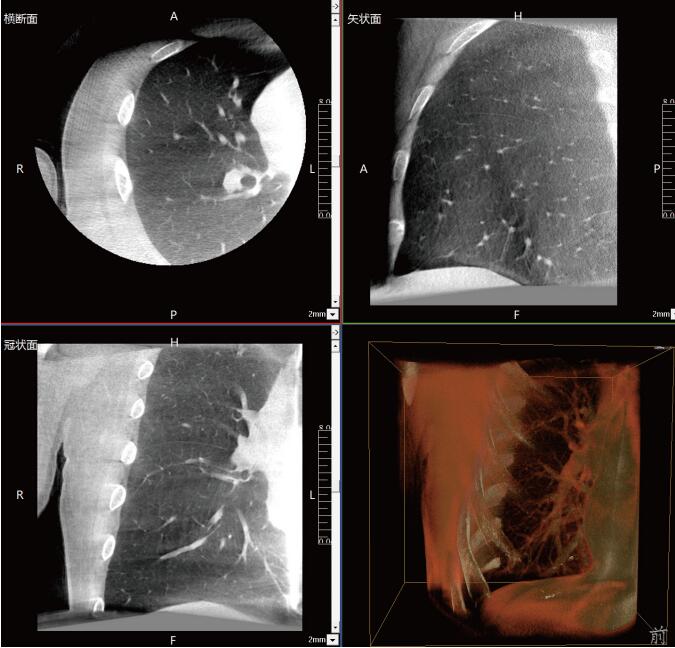

一站式“術(shù)中CT”,肺部診斷+治療新選擇

滿足肺結(jié)節(jié)活檢、肺結(jié)節(jié)切除、肺結(jié)節(jié)消融治療等各類術(shù)式的術(shù)中影像要求:

常規(guī)流程下需要術(shù)前CT室內(nèi)的引導(dǎo)定位,再轉(zhuǎn)入手術(shù)室進(jìn)行胸腔鏡手術(shù),在轉(zhuǎn)運(yùn)過程中有氣胸、肺出血和導(dǎo)針脫落的風(fēng)險(xiǎn)。使用大功率平板三維C形臂PLX C7600,可在手術(shù)室內(nèi)一站式完成肺部三維影像重建,在穩(wěn)定呼吸的條件下,亞亳米級(jí)定位肺結(jié)節(jié)位置,有效規(guī)避穿刺路徑附近的血管、氣管等重要解剖結(jié)構(gòu),術(shù)中確保穿刺安全有效。同時(shí)可大幅降低輻射劑量,減少射線對(duì)醫(yī)患的傷害。